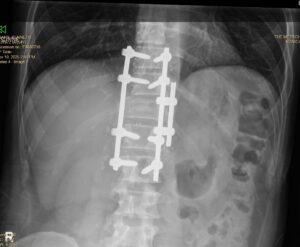

I broke my back.